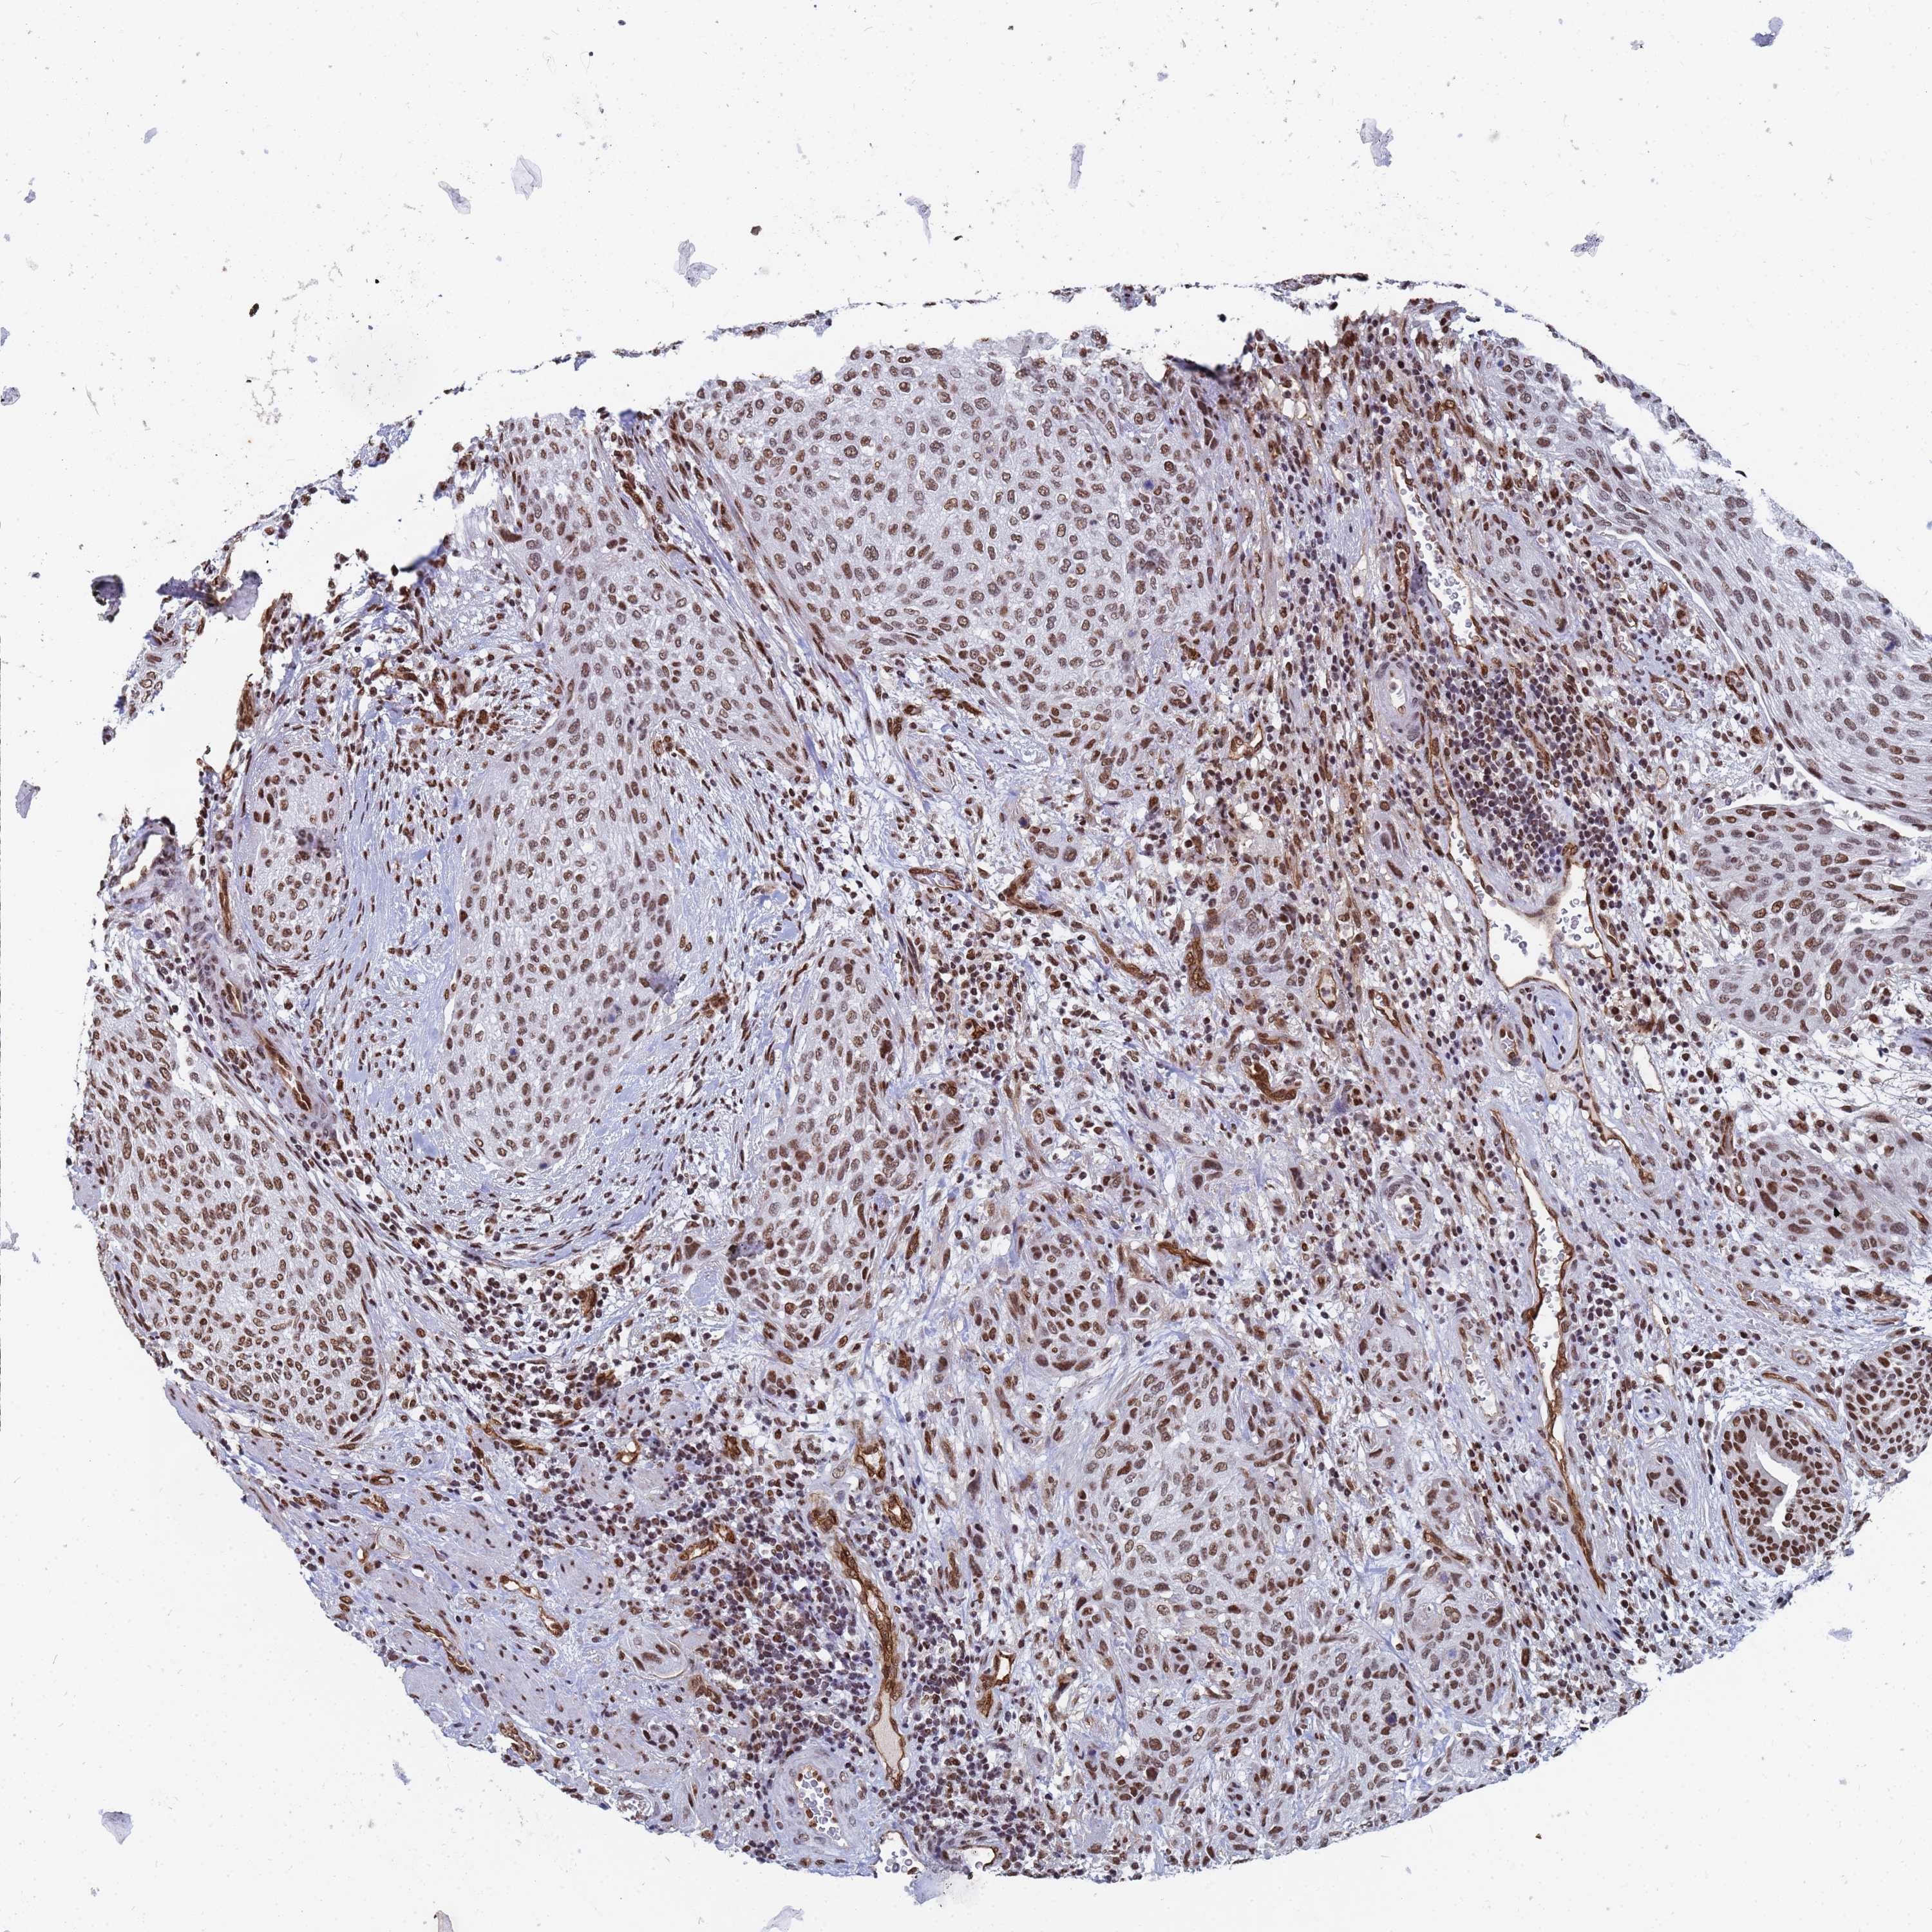

UROTHELIAL CANCER - Protein expressioni

A mouse-over function shows sample information and annotation data. Click on an image to view it in a full screen mode. Samples can be filtered based on level of antibody staining by selecting one or several of the following categories: high, medium, low and not detected. The assay and annotation is described here.

Note that samples used for immunohistochemistry by the Human Protein Atlas do not correspond to samples in the TCGA dataset.

Antibody stainingi

Antibody staining in the annotated cell types in the current human tissue is reported as not detected, low, medium, or high, based on conventional immunohistochemistry profiling in selected tissues. This score is based on the combination of the staining intensity and fraction of stained cells.

Each image is clickable and will lead to virtual microscopy that enables deeper exploration of all samples and also displays staining intensity scores, fraction scores and subcellular localization as well as patient and tissue information for each sample.

Antibody HPA045785

Staining

High

Medium

Low

Not detected

Intensity

Strong

Moderate

Weak

Negative

Quantity

>75%

75%-25%

<25%

None

Location

Nuclear

Cytoplasmic/membranous

Cytoplasmic/membranous,nuclear

Urothelial carcinoma, High grade

Urothelial carcinoma, Low grade